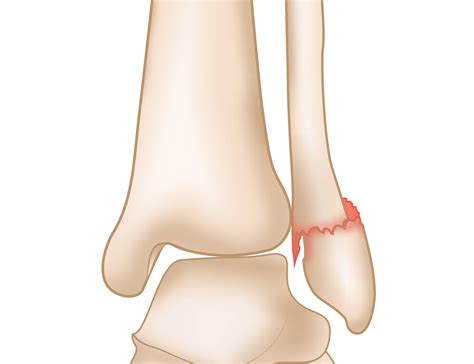

Fractures

Fractures of the lateral malleolus can occur due to direct trauma, such as a fall or a blow to the ankle. These fractures can range from minor cracks to complete breaks and may require surgical intervention depending on the severity.

Symptoms of a lateral malleolus fracture may include:

• Severe pain and tenderness

• Swelling and bruising

• Deformity or misalignment of the ankle

• Inability to bear weight on the affected foot